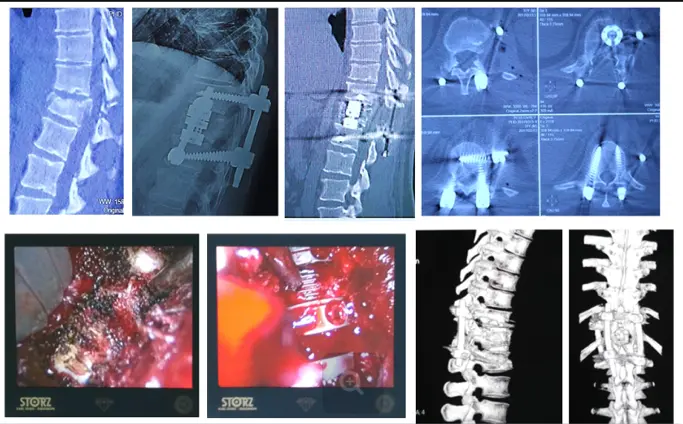

Транспедикулярная мини-инвазивная стабилизация и бисегментарный межтеловой спондилодез с видеоэндоскопической ассистенцией при компрессионно-оскольчатом переломе первого поясничного позвонка.

Компрессионно-оскольчатый перелом второго поясничного позвонка. Циркулярный спондилодез 360 градусов с видеоэндоскопической ассистенцией.